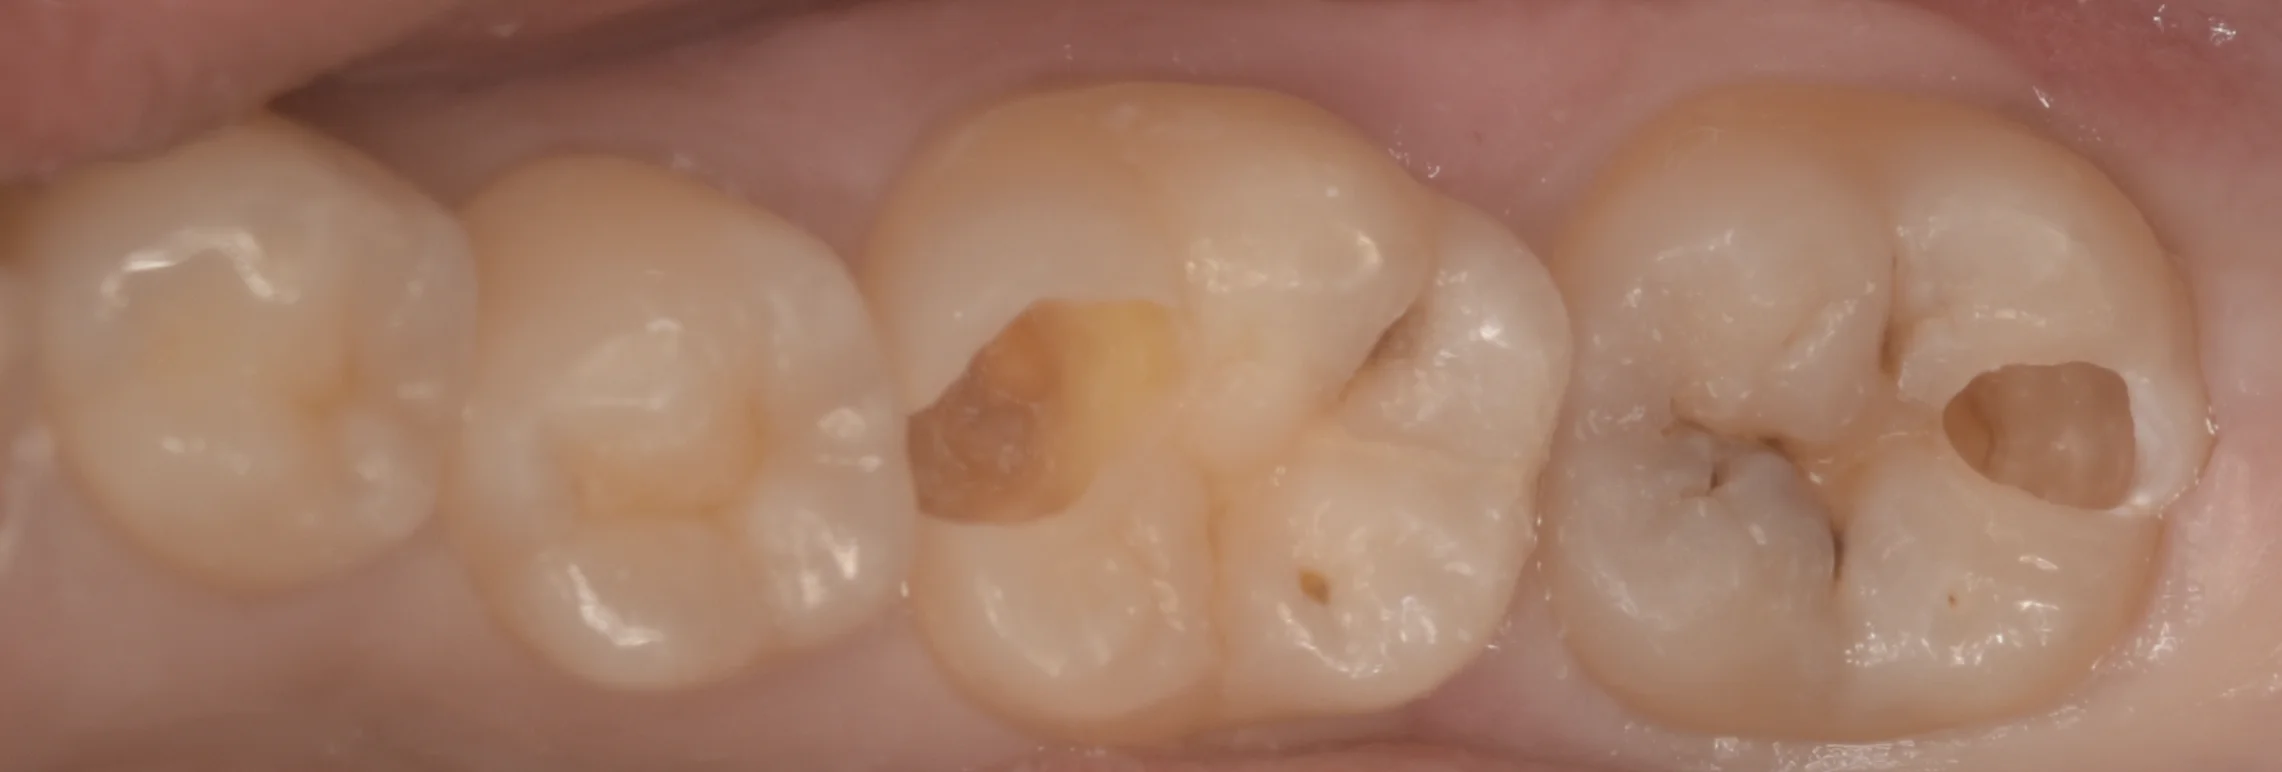

まずは術前からです。

右側2本の治療を行いました。

そのうち、右から2番目は手前の歯側の色が少し変になっているのがわかると思います。

一番右の歯は溝の部分に黒い箇所がいくつかありますね。

虫歯を見やすくするために軽く削ったのがこちらになります。

どちらも内部で非常に大きく深くなっていました。